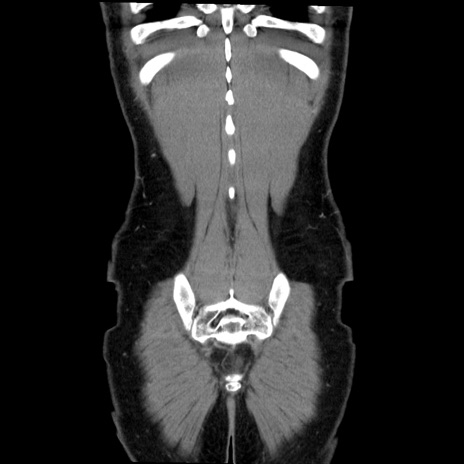

症例36(冠状断像)

【症例】20歳代 男性

【主訴】心窩部痛

【現病歴】今朝より上腹部痛あり。一旦軽快していたが再度出現したため救急要請。昨日夕に白身の魚を含む刺身を食べた。

【身体所見】BP 136/89mmHg、HR 74/min、BT 37.0℃、腹部:膨満、軟、心窩部に圧痛あり。反跳痛なし、筋性防御なし、腸雑音やや亢進あり。

【データ】WBC 17700、CRP 0.48